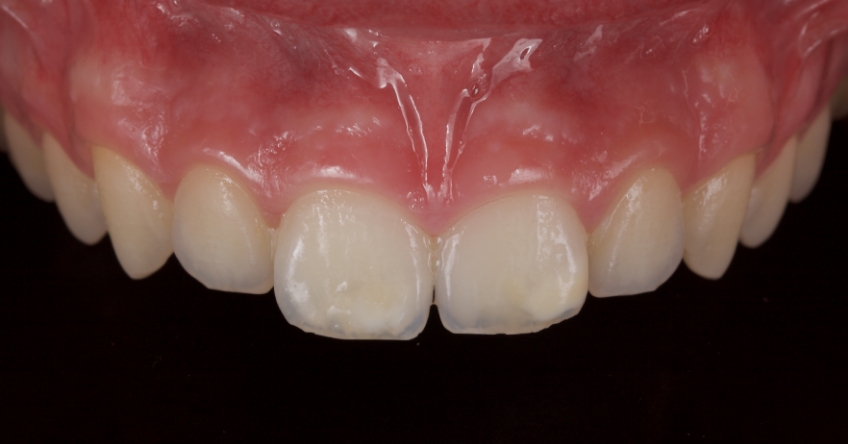

Case #2: Restoration With Direct Composite Resin

This 21-year-old male presented with an uncomplicated enamel-dentin fracture of the upper right central, lateral incisor, and canine following a fall.